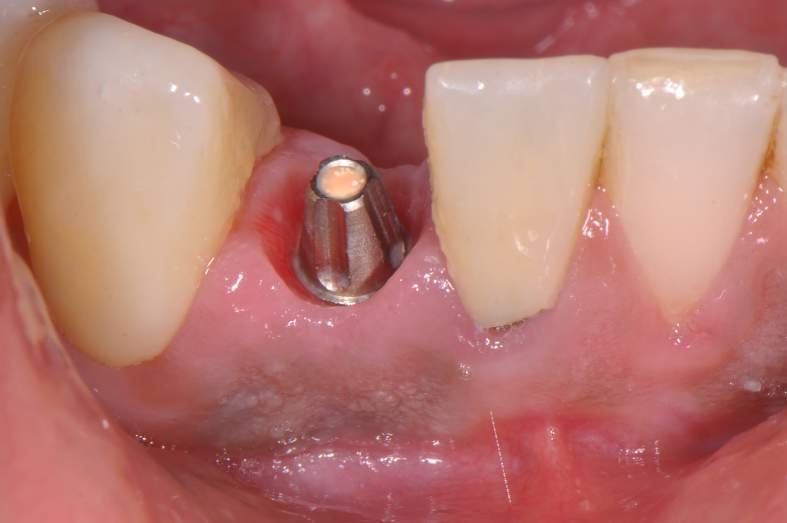

Implantes estreitos de titânio surgiram na Implantodontia com a indicação clássica de serem utilizados para substituição de incisivos laterais superiores, incisivos inferiores (Fig.1), espaços edêntulos pequenos e com baixa incidência de carga mastigatória.

O implante Slim Pilar de corpo único com os diâmetros de 2,5 e 3,0 milímetros (Fig. 2) foram desenvolvidos para superar o desafio de pequenos espaços desdentados.

Um implante de corpo único não tem interface entre o corpo do implante e pilar protético, e, por conseguinte, a perda óssea crestal inicial e ao longo do tempo pode ser reduzida. 5,6

Como o implante perde pouco osso proximal quando posicionado na altura da crista óssea, o implante pode ser colocado tão próximo quanto 1 mm a raiz do dente adjacente.2 Portanto, o espaço mesio-distal um implante de 3,0mm de diâmetro, por exemplo, pode ser tão pequeno como 5,0mm. As principais indicações para os implantes dessas dimensões são: